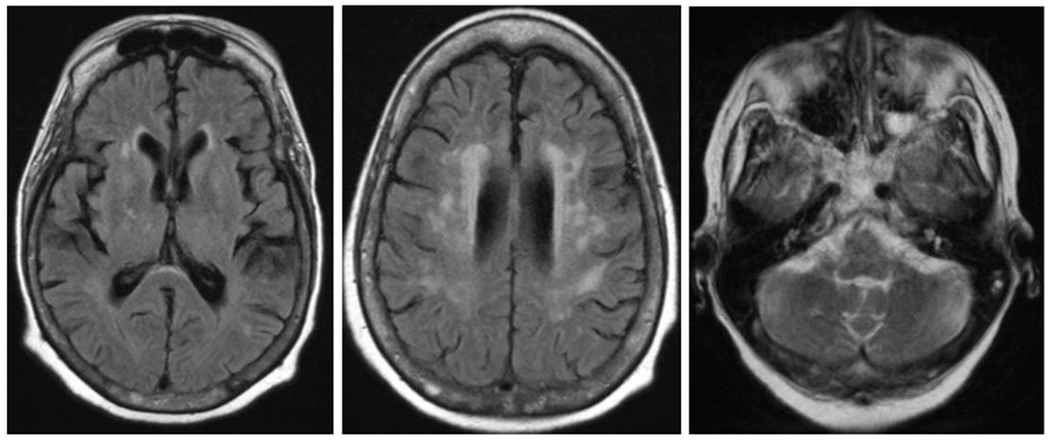

Cache Valley virus (CVV) is a mosquito-borne virus that is a rare cause of disease in humans. In the Fall of 2020, a patient developed encephalitis six weeks following kidney transplantation and receipt of multiple blood transfusions.

CVV was detected in CSF from the index patient by mNGS, and this result was confirmed by RT-PCR, viral culture, and additional whole genome sequencing. The organ donor and other organ recipients had no evidence of infection with CVV by molecular or serologic testing. Neutralizing antibodies against CVV were detected in serum from a donor of red blood cells received by the index patient immediately prior to transplant. CVV neutralizing antibodies were also detected in serum from a patient who received the co-component plasma from the same blood donation.

Our investigation demonstrates probable CVV transmission through blood transfusion. Clinicians should consider arboviral infections in unexplained meningoencephalitis after blood transfusion or organ transplantation. The use of mNGS testing might facilitate detection of rare, unexpected infections, particularly in immunocompromised patients.